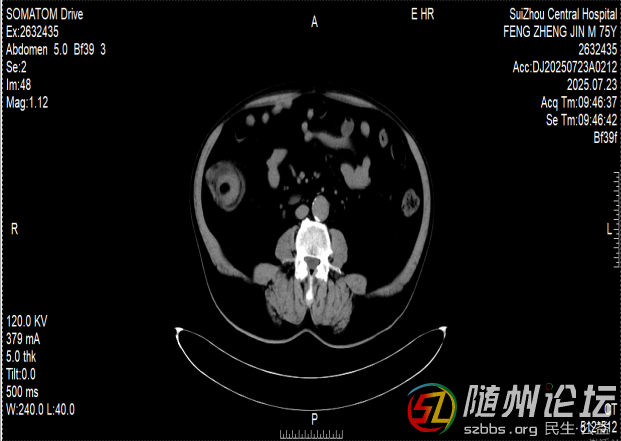

一位76歲的患者,近半年來飽受排便困難的折磨,輾轉(zhuǎn)多家醫(yī)院后,最終在隨州市中心醫(yī)院找到了病因——他的小腸末端,藏著一個直徑達6厘米的巨大腫瘤。

這個腫瘤就像一顆“定時炸彈”,已多次引發(fā)腸梗阻和腸套疊,導(dǎo)致老人無法正常進食,痛苦不堪。由于年事已高,傳統(tǒng)的開腹手術(shù)創(chuàng)傷大、恢復(fù)慢,家屬顧慮重重。

兩難之際,老人在家屬的陪同下找到了隨州市中心醫(yī)院消化內(nèi)鏡中心主任陳志勇。仔細評估病情后,陳志勇認為,盡管腫瘤巨大、位置特殊,手術(shù)風(fēng)險很高,但仍有希望通過內(nèi)鏡微創(chuàng)切除,讓患者避免開腹之痛。